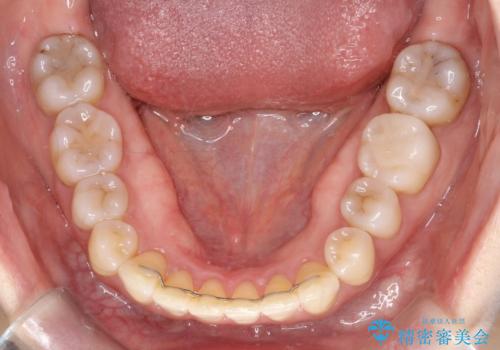

- 前歯の凸凹を主訴に来院されました。

インビザライン にて治療を行い、歯並びが綺麗になったと満足していただきました。

前歯のガタガタの量が多かったため、IPR(歯のサイズを小さくするための処置)を行なって治療しました。